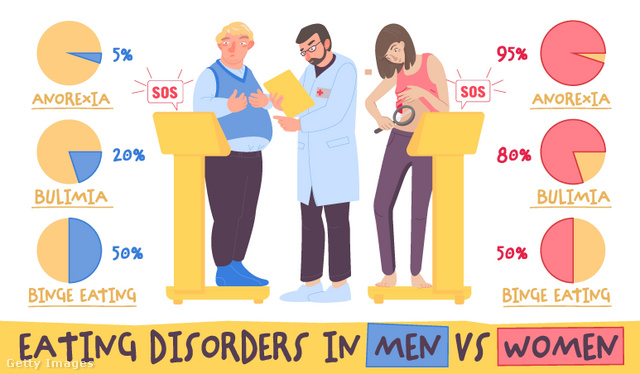

a depresszió, szorongás, evészavar és személyiségzavar, de még a nikotinfüggőség is gyakoribb volt.

Konkrét és meglepő eredményekre a két nem és a különböző pszichés zavarok kialakulásának kapcsolatát analizálva bukkantak.

Férfiak

Közel kétszer annyi férfi szenvedett nikotinfüggőségtől, mint nő. Az obes férfiak közül kétszer annyi mutatott depressziós tüneteket, mint normál testsúlyú férfitársaik között. Az elhízott urak egyúttal hajlamosabbaknak bizonyultak a skizofréniára is.

Nők

Az elhízott nők között háromszor annyi volt a depressziós, mint az átlagos testsúlyúak körében, és az eredmények tükrében, jobban ki vannak téve a szorongás kialakulásának is.